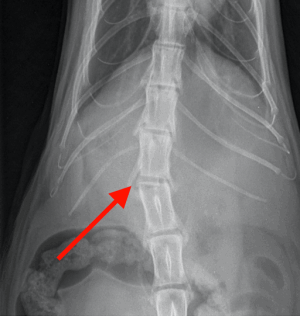

Osiris presented to Hamilton Specialist Referrals (HSR) as an emergency following a fall from height. Sadly, he was unable to use his back legs. His first opinion veterinary practice promptly identified that Osiris was paraplegic and acquired some radiographs of his back. These revealed a high suspicion of a spinal fracture at the location identified by the red arrows on the below images.

Osiris was assessed by our anaesthesia team and nurses who stabilised him so that he could be anaesthetised. Under a general anaesthetic, a CT of the back confirmed the fracture in his spine (red arrow on images below). The vertebral canal (green star) is where the spinal cord runs. The floor of the vertebral canal (blue lines) should be level and as you can see in the images there is a step in the floor, resulting in pressure on the spinal cord. The image on the right also shows a deviation in the spine (the purple lines should be straight), also adding pressure to the spinal cord. This pressure means that the neurotransmission pathway between the brain and legs is disrupted, which ultimately meant that Osiris couldn’t use his hindlimbs.